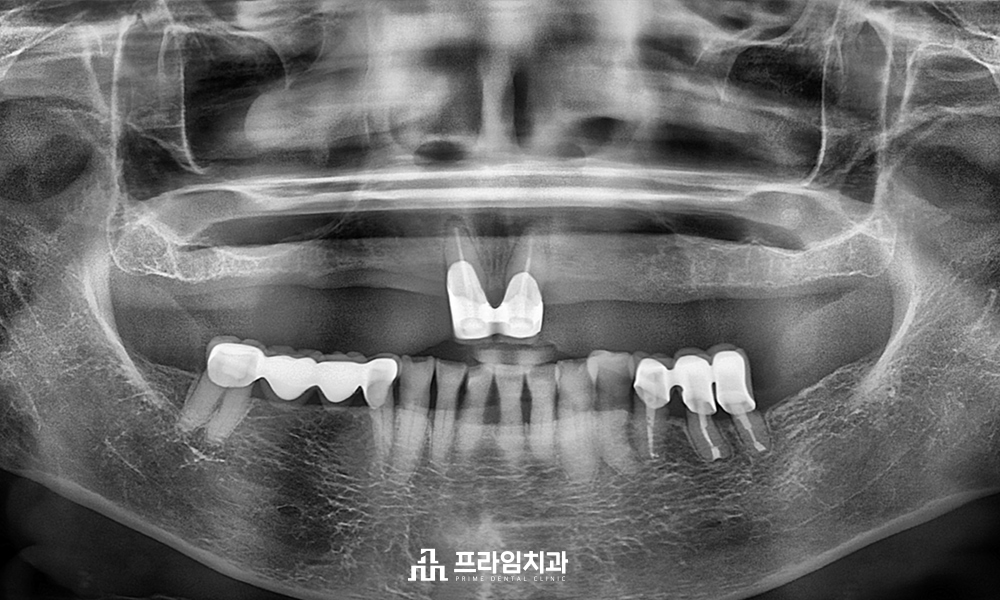

수술 후 9년이 지난 2022년 사진입니다. 뿌리에 염증이 억고, 치아 역시 제 기능을 할 수 있는 양호한 상태였습니다.

위 분은 2013년 항암치료 후 내원하셨는데요, 어금니가 아미 많이 상해 치아가 녹고 파인 상태였습니다. 발치 후 임플란트가 필요한 상황이었지만 여러 번의 권유에도 임플란트에 대한 거부감이 심해, 임플란트 치료가 불가능하였습니다.

재신경치료는 치아의 뿌리까지 연결 통로를 관통시켜주는 것이 중요한데, 현재 상황에서 불가능하여 뿌리 끝의 염증을 제거하기 위해 의도적재식술을 시행하였습니다. 시행 중 치아 뿌리가 분리되면서 큰 어금니 한 개가 작은 어금니 두개로 분리되었습니다.

맨 뒤 사랑니는 제거한 상태입니다. 자연치를 살리기 위한 방법으로는 재근관치료, 치근단 절제술, 의도적재식술, 치근 분리술, 치관 확장술, 포스트&코어가 있는데요, 하나의 치아를 위해 상기 치료가 모두 적용되었습니다.